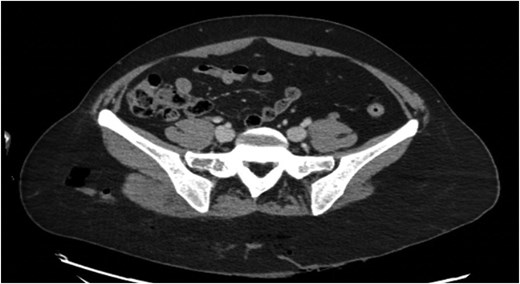

CT scan showed a perineal and gluteal laceration with concern for anal rupture, extensive subcutaneous emphysema of the right gluteal region (Fig. 1), and a small right subcutaneous hematoma. The patient was taken to the operating room for washout and repair.

Preoperative pelvic CT scan showing right gluteal subcutaneous emphysema.